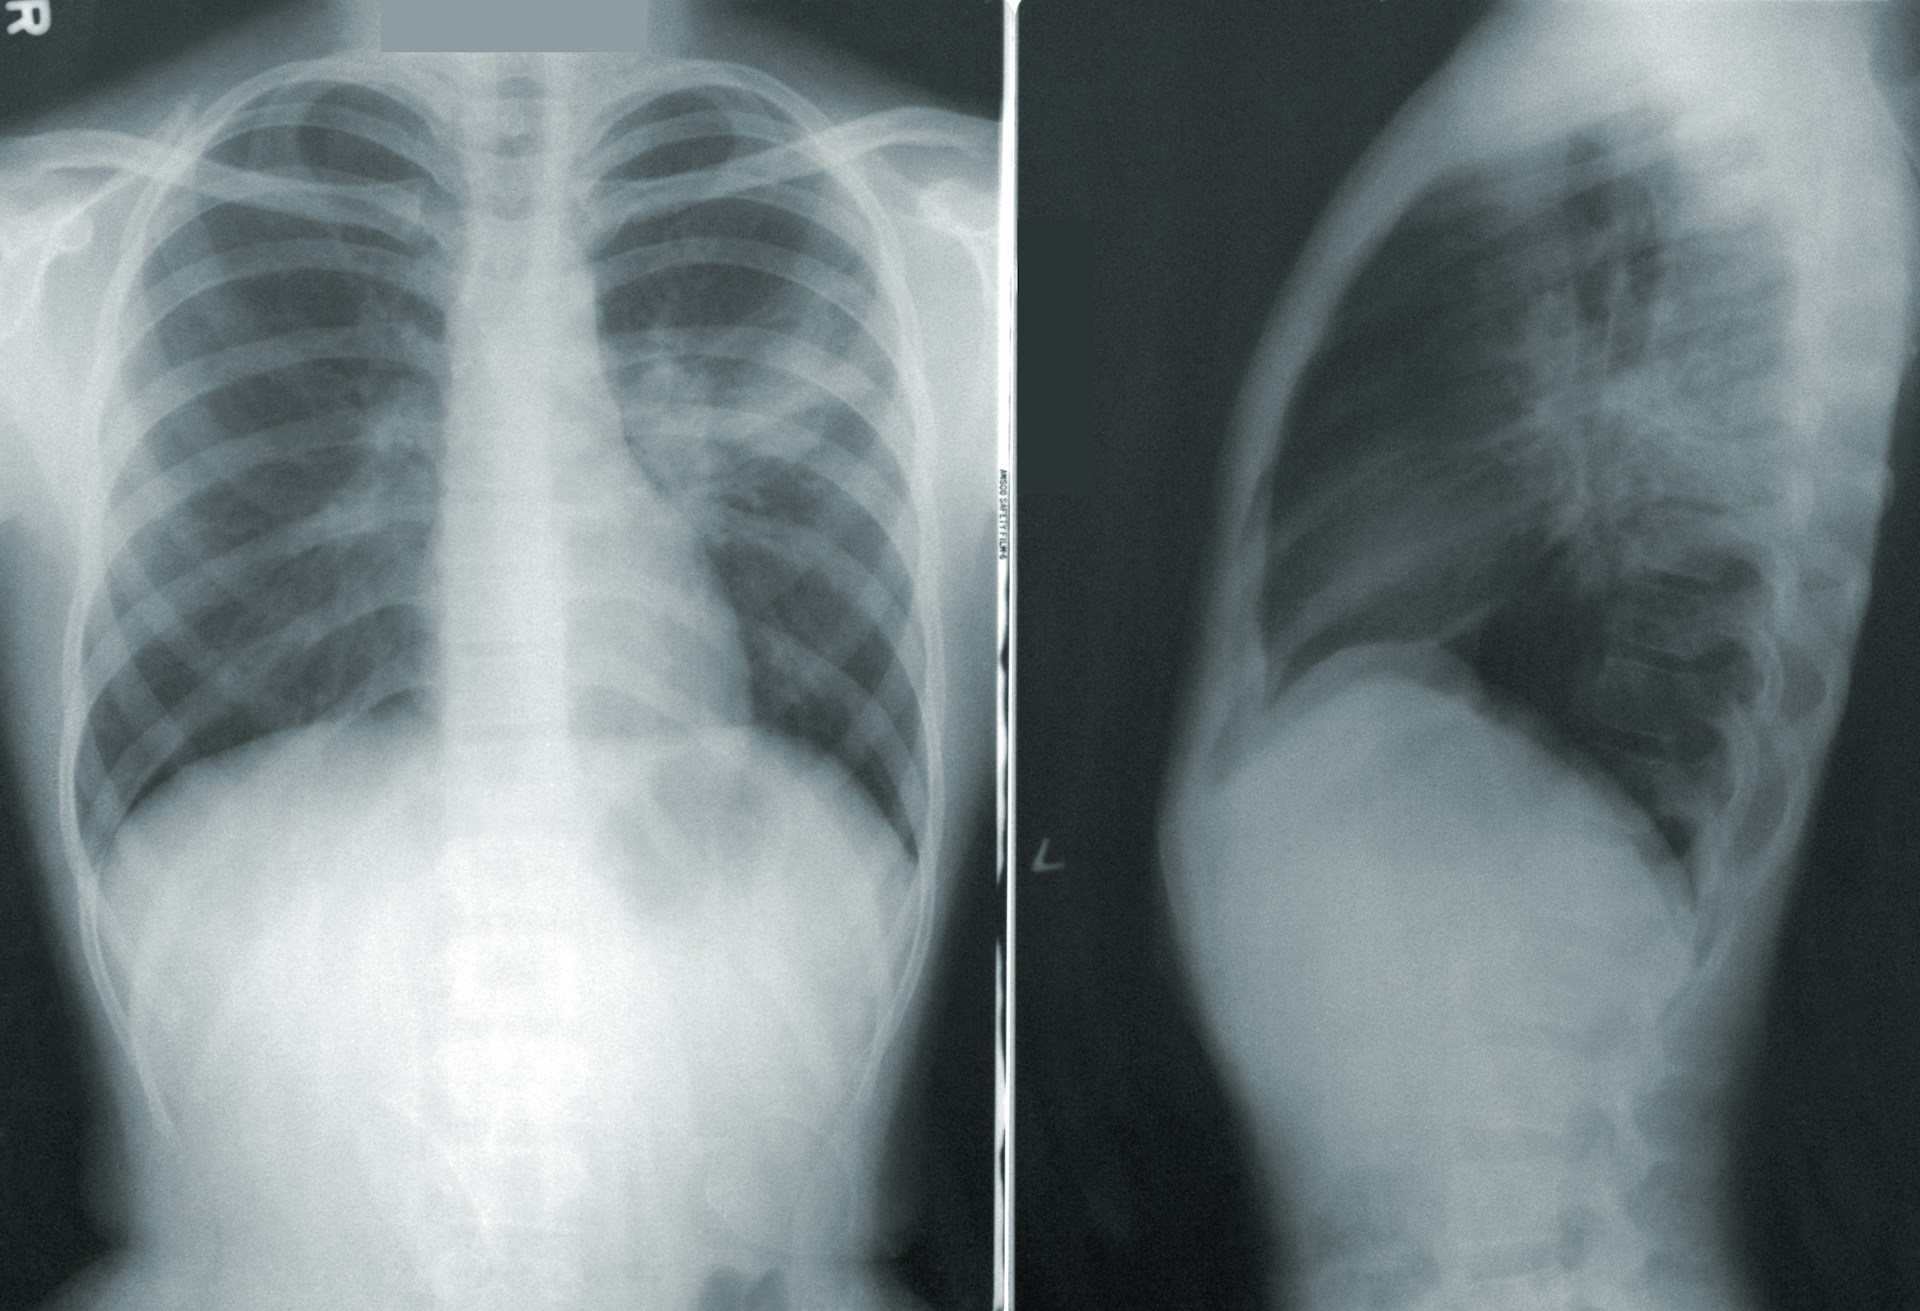

[1단계: 급성폐렴이란?]급성폐렴(acute pneumonia)은 폐의 조직에 급격한 염증이 생기는 호흡기 질환으로, 바이러스, 세균, 진균 등 다양한 병원체에 의해 발생합니다. 감염 원인에 따라 증상이 다르지만, 보통 고열, 기침, 가래, 숨 가쁨 등의 증상이 대표적으로 나타납니다. 면역력이 약해진 시기나 독감이 유행하는 계절에는 발병 위험이 특히 높습니다. 무엇보다 급성폐렴은 진행 속도가 빠를 수 있어, 조기 발견과 적절한 치료가 매우 중요합니다. 특히 노인, 영유아, 그리고 심장질환이나 당뇨와 같은 기저질환이 있는 경우에는 증상이 빠르게 악화되거나 합병증이 생길 수 있으므로 각별한 주의가 필요합니다. 또한 폐렴은 정확한 진단 없이 감기나 독감으로 잘못 생각하기 쉬워, 치료가 지연될 수도 있습니다. ..